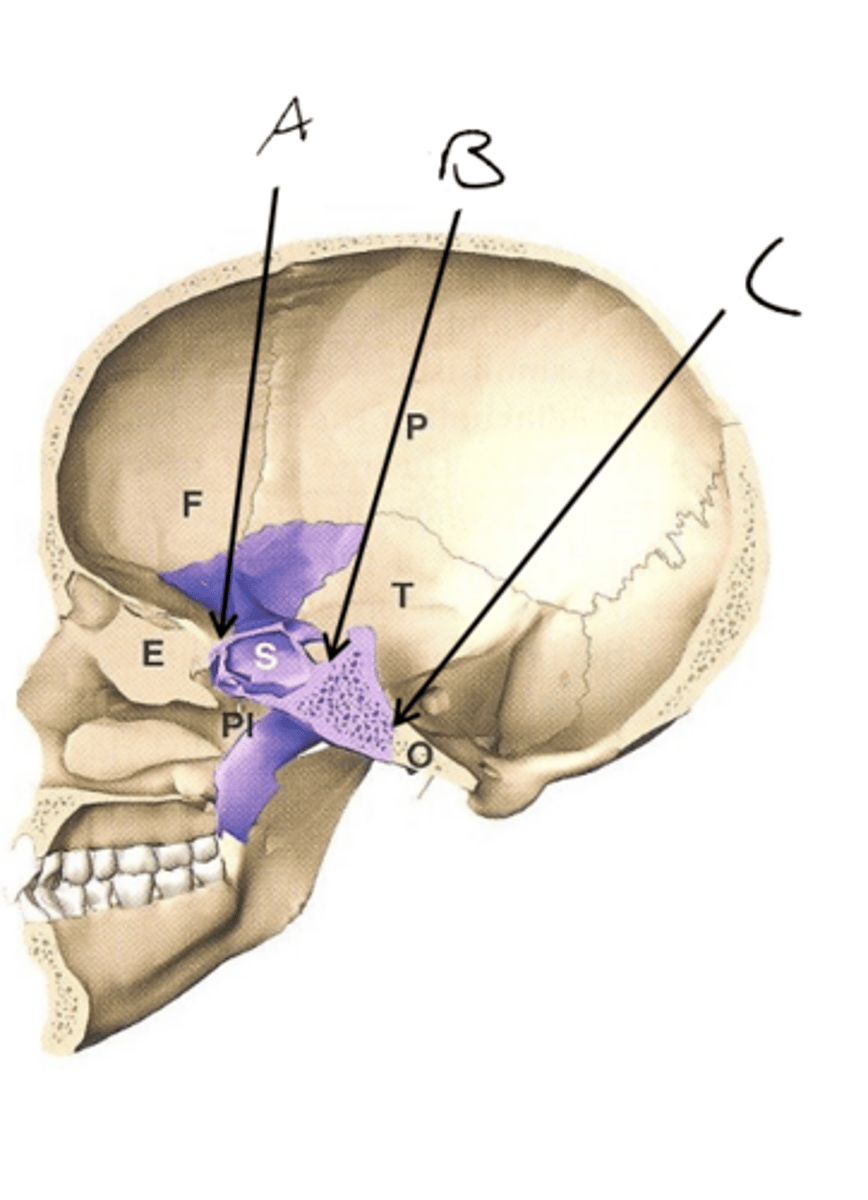

A. SES

B. MSS

C. SOS